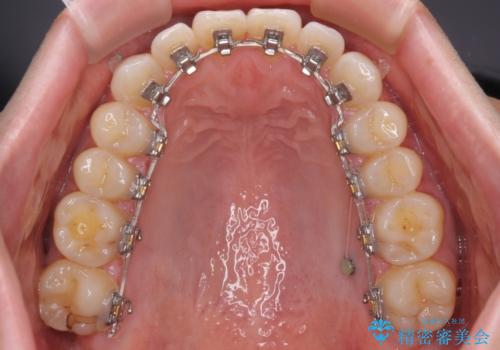

- 矯正装置

- ハーフリンガル

自己管理の大変なインビザラインや、目立つ表側のワイヤー矯正は避けたいとのことで、

上顎だけ裏側装置のハーフリンガルにて矯正しました。